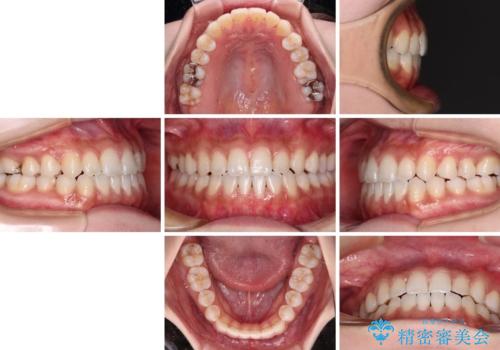

舌突出癖で口元が開いてしまう 舌トレーニングを行ったインビザライン矯正

インビザラインにより上下の前歯の隙間を閉じていくこととしました。

上下の隙間に舌が入り込むことが、すきっ歯やオープンバイトの原因であったため、舌の筋肉のトレーニングも並行して行い、後戻りの抑制を図りました。